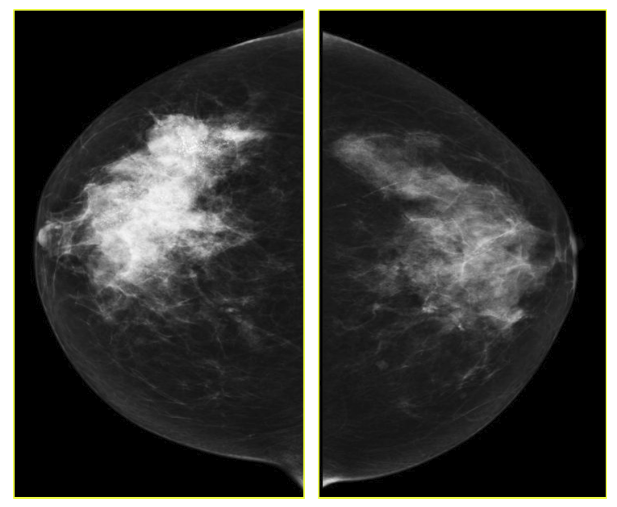

The goal of screening asymptomatic women is to find breast cancer in its earliest stages when treatment has the highest chance for survival. For diagnosis and characterization of primary breast lesions, anatomical imaging such as mammography is the most common screening test for breast cancer, which is basically an x-ray picture of the breast. Examples of mammography images are shown in Fig. 1 for a 67 year old patient. Mammography may find tumors that are too small to feel. It may also find ductal carcinoma in situ (DCIS) [10]. Mammography is more averse to discover breast tumors in women with dense breast tissue. Since both tumors and dense breast tissue seems white on a mammogram, it is hard to find a tumor when there is a dense breast tissue. The mammography sensitivity varies in the range depending on the age of the examined group and number. This range for sensitivity varies from 80% to 96% and in case of specificity it is in the range of 15 to 51.8% [11].